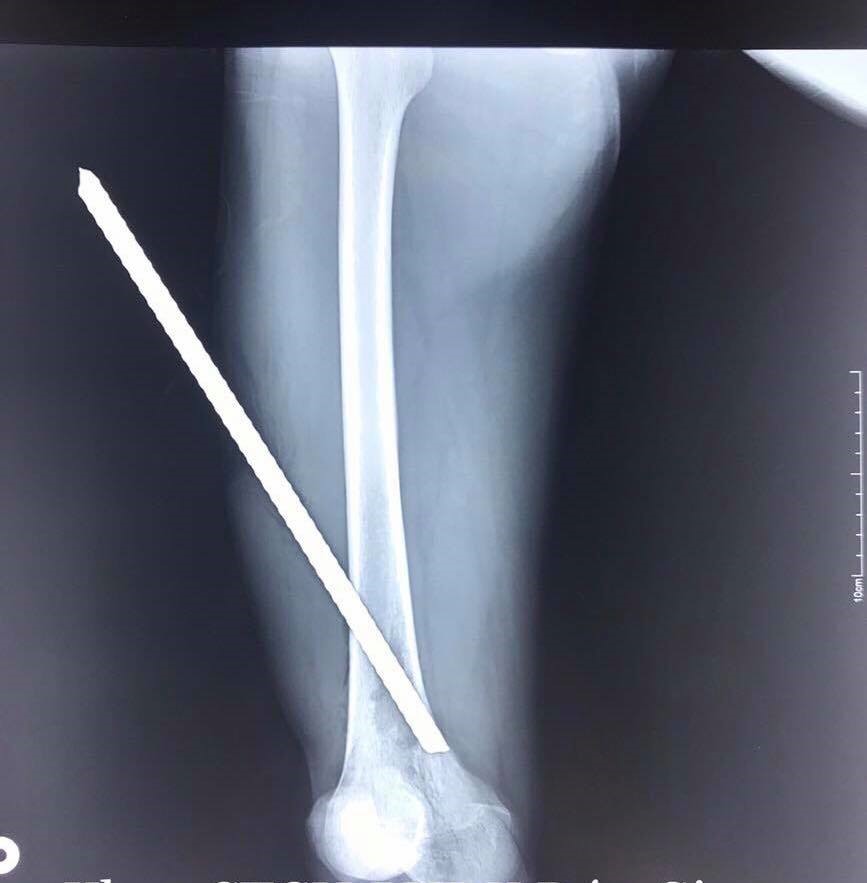

Ngày 28/1, Bệnh viện đa khoa Đức Giang, Hà Nội cho biết, bệnh nhân Lê Văn Quý (SN1993 ở Gia Lâm, Hà Nội) vừa được cấp cứu thành công sau ca tai nạn lao động. Bệnh nhân ngã từ giàn giáo cao khoảng 3 mét xuống, chân cắm vào thanh sắt 10 dưới sàn bê tông.

Thời điểm gặp tai nạn, bệnh nhân được đồng nghiệp dùng máy cưa để cắt rời đoạn sắt ra khỏi sàn bê tông rồi đưa đến viện cấp cứu.

Hình ảnh thanh sắt đâm xuyên qua nhiều vùng ở chân |

Bệnh nhân Quý nhập viện trong tình trạng thanh sắt xuyên từ mặt ngoài đoạn giữa đùi xuống dưới và ra sau, chọc thủng các lớp cơ ở đùi trượt qua xương xuyên xuống vùng nguy hiểm là vùng khoeo chân (nơi có các mạch máu và các dây thần kinh đi qua).

Sau khi tiến hành chụp chiếu, các bác sĩ tiến hành phẫu thuật cho bệnh nhân. Quá trình các bác sĩ phẫu thuật đã bộc lộ đầu trong của thanh sắt thấy nhiều đất cát, dầu mỡ, đầu thanh sắt sắc nhọn nhưng rất may còn cách các mạch máu và các dây thần kinh vài mm. Bệnh nhân đã được rút bỏ thanh sắt và cắt lọc hết tổ chức dập nát, lấy sạch dầu mỡ đất cát trong vết thương.

Hiện bệnh nhân đang hồi phục.